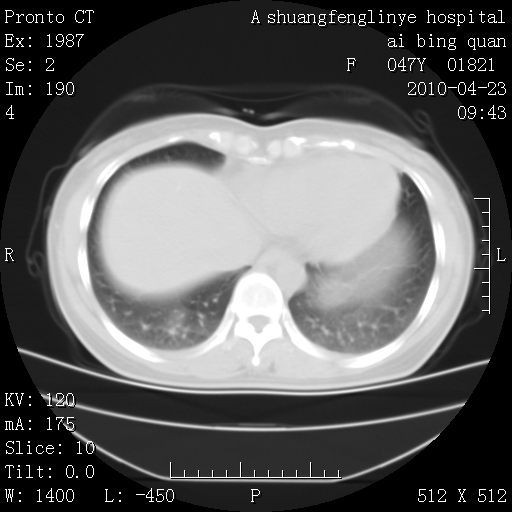

标题: CT25944:胸痛、气短、前几日高烧!肺Ca?请会诊! [打印本页]

标题: CT25944:胸痛、气短、前几日高烧!肺Ca?请会诊!

双肺多发结节,考虑转移瘤,肺癌肺转移不除外

双肺多发结节,部分密度较高,最大结节边缘光滑。临床有“胸痛、气短、前几日高烧”病史。首选考虑:右肺感染性病变!建议积极消炎后复查!